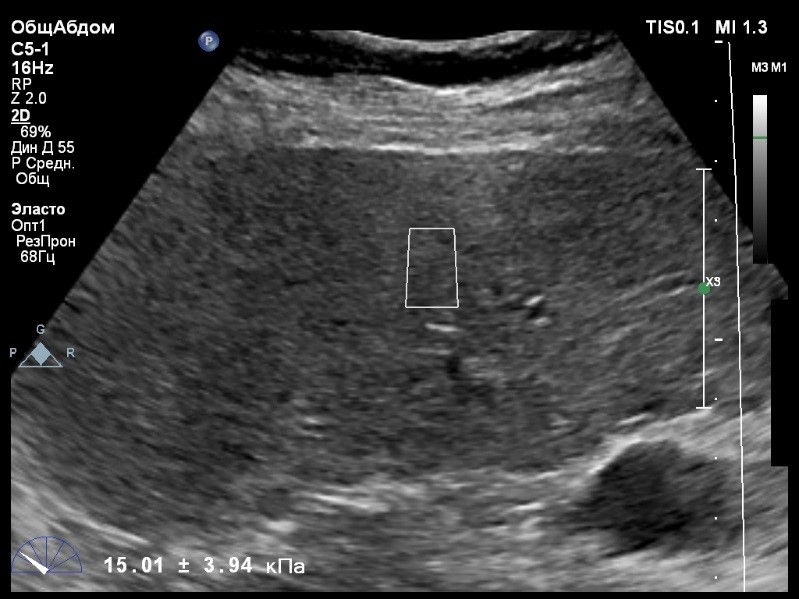

В виду технических сложностей выполнения исследования (избыточная масса тела), для оценки жесткости была выбрана технология компании Philips ElastPQ (точечная эластография) и прибор компании Philips Epiq 7. Исследование было проведено в соответствии с клиническими рекомендациями для ультразвуковых приборов компании Philips. В результате исследования были получены следующие результаты:

| 1 [16.86] kPa | 2 [15.14] kPa | 3 [12.83] kPa |

| 4 [12.81] kPa | 5 [13.07] kPa | 6 [15.01] kPa |

| 7 [16.95] kPa | 8 [14.06] kPa | |

Стандартное Отклонение [1.62] kPa Медиана Жесткости [14.54] kPa Фактор Качества IQR/Med 12%

Зона интереса расположена на более чем на один сантиметр глубже капсулы, параллельно ходу луча, в середине изображения, в участке печени лишенном артефактов

Капсула видна как яркая белая линия перпендикулярная ходу ультразвукового луча.

Стандартное отклонение (3,94 kPA) не превышает 30 процентов от полученного значения (15,01 kPA).

Для интерпретации полученных клинических данных были использованы Рекомендации по проведению эластографии сдвиговой волной для оценки жесткости печени при использовании ультразвуковых аппаратов компании Филипс с примером протокола. Стоит отметить, что для проведения исследования у технически сложного пациента был выбран аппарат экспертного класса. Подготовка пациента соответствовала проводимому исследованию. Представленные слайды проведенного исследования свидетельствуют о правильном техническом исполнении проб, что позволяет заключиться о достоверности полученных измерений. Таким образом, учитывая полученную медиану жесткости на уровне 14,54 кРа (12.83-16.95 kPa) и уровень стандартных отклонений не превышающих 30%, полагаю, что уровень степени фиброза соответствует стадии F4. Заведующий отделением УЗД МЦ «Асклепий», Глушенко Д. Е.